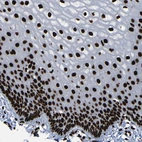

Immunohistochemical staining of human endometrium shows moderate to strong nuclear positivity in glandular cells.